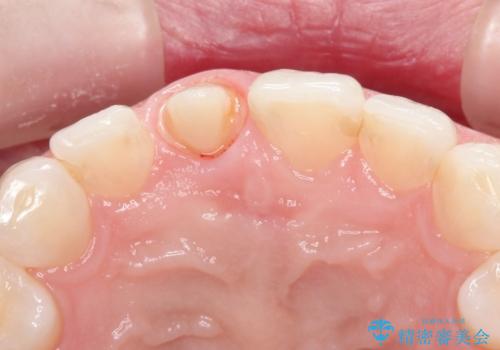

- 「他院で治療した前歯の被せものが一か月の間に2回外れたのでやり変えたい」を主訴に来院されました。

10年前に根管治療を他院で行っており、根尖性歯周炎の予防のため根管治療から行いました。被せものはオールセラミッククラウンで治療を行いました。

10年前にラバーダムシート無しに根管治療を行っており、現在、症状は出ていませんが、根尖性歯周炎の予防のため根管治療から行いました。ホームホワイトニングを2週間行って頂き、その後、オールセラミッククラウンで治療を行っています。

※根尖性歯周炎は根管内の細菌が原因となり発症します。唾液の中には数千億個もの細菌が存在します。したがって、ラバーダムシートを使用し、歯を唾液から守ってあげることが大切になります。当院では、ラバーダムシートの使用に加え、マイクロスコープ(歯科用顕微鏡)、P-MAX(超音波洗浄の機械)を使用して治療を行っています。

※ファイバーコアとは、根管治療後、歯に立てる土台の事です。金属の土台と比べ歯根破折のリスクが低く、白いのが特徴です。